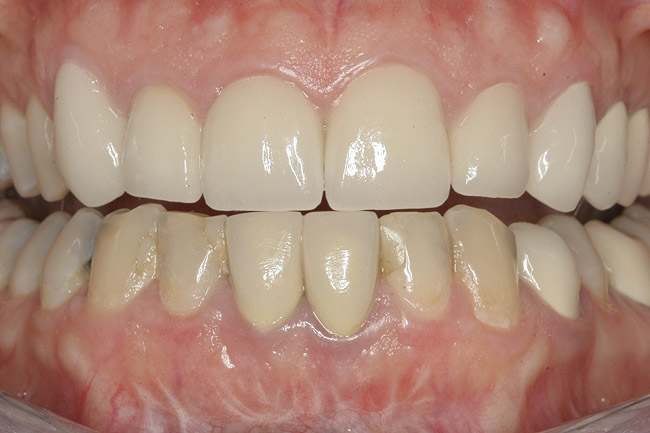

Figure 1  Initial presentation with yellow, poorly color-matched restored mandibular anterior teeth.

Figure 1

A 36-year-old nonsmoking Caucasian woman in good health presented to the author’s periodontal practice to replace tooth No. 26 with an implant. She had presented to her restorative dentist with a chief complaint of yellow, poorly color-matched mandibular anterior teeth (Figure 1). Her medical history was significant for asthma and seasonal allergies for which she took oral montelukast, orally inhaled fluticasone and salmeterol, and oral cetirizine; she also took lorazepam for anxiety. Her dental history was significant for traumatic experiences.